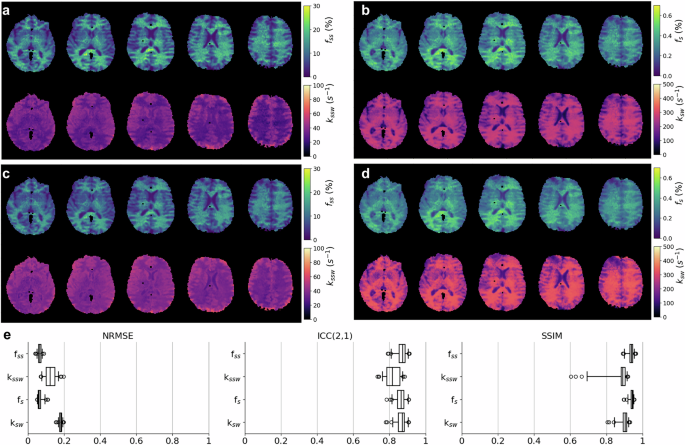

The joint fit and training of the NBMF produced a neural reconstructor, optimized on a single subject. We then re-applied the trained reconstructors to additional subjects in a fast inference mode. A representative example comparing the parameter maps obtained from single-subject NBMF with those obtained by a rapid reconstructor reuse is shown in Fig. 5. The resulting agreement metrics (Fig. 5e) were as follows; NRMSE: 7 ± 1%, 12 ± 3%, 7 ± 1%, and 18 ± 1%; Intraclass correlation coefficient ICC(2,1): 0.87 ± 0.03, 0.82 ± 0.04, 0.86 ± 0.03, 0.86 ± 0.03; SSIM: 0.93 ± 0.02, 0.87 ± 0.07, 0.94 ± 0.01, 0.90 ± 0.03, for the fss, kssw, fs, and ksw, respectively. Additional analysis is provided in Supplementary Fig. 4.

A comparison between the results of single-subject NBMF (a, b) and real-time quantification of the same subject by inferring the neural reconstructor trained while fitting another subject (c, d). A perceptually and quantitatively similar outputs were obtained for both semisolid (a, c) and amide (b, d) exchange parameters mapping. e Similarity analysis using normalized root-mean-square (NRMSE), intraclass correlation coefficient (ICC(2,1), absolute agreement-assessing variant), and structural similarity index measure (SSIM) across all (n = 50) processed brain slices. In box plots, the central horizontal lines represent median values, box size represents the two central (2nd, 3rd) quartiles, whiskers represent 1.5× the interquartile range above and below the upper and lower quartiles, and circles represent outliers.